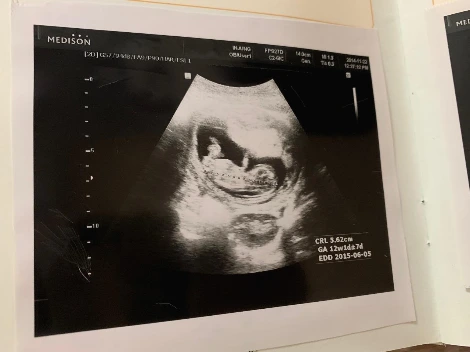

아기 인형까지 앞에 앉혀다 놓고 열심히 초음파 사진을 보고 있는 5세 아동

아이는 나에게 주수마다 초음파 사진이 붙어 있는 산모수첩을 들고 와 물었다.

"엄마 이 콩 같은 게 나야?"

응, 그렇지. 이 콩이 너였지. 웃음이 난다.

아이가 생각보다 더 신기해하길래 내친김에 초음파 동영상도 보여주었다. 아이는 뱃속 본인의 자세를 따라 하며 웃고 난리가 났다. 나는 즐거워하는 아이 옆에서 새삼 추억에 젖는다.

임신 테스트기에서 두 줄을 봤던 아침, 병원에서 임신 확정을 받고 남편에게 전화하던 길, 생각보다 또렷하고 강렬했던 태아의 심장소리, 4센티도 안 되는 몸에 팔다리가 생겨 젤리 곰같이 귀여웠던 초음파 사진, 아이를 막 낳고 거친 숨을 몰아쉬고 있는데 아이가 생각보다 너무 못생겨서 충격(?) 받았던 새벽...